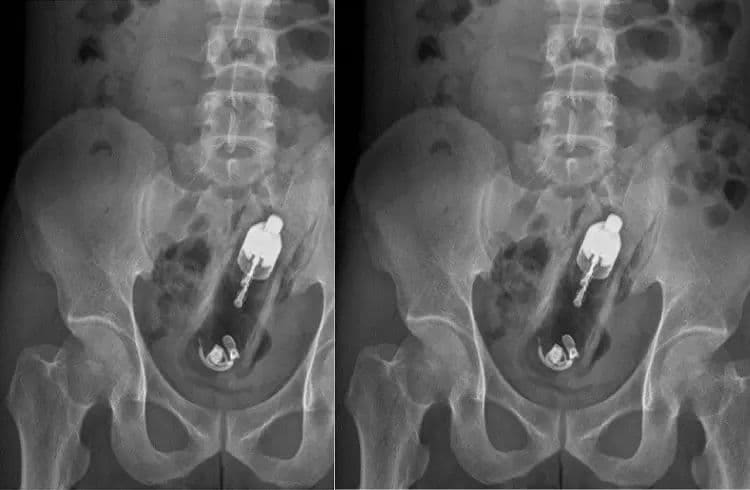

Shocking : ಯುವಕನೊಬ್ಬ ಲೈಂಗಿಕ ತೃಪ್ತಿಗಾಗಿ ತನ್ನ ಖಾಸಗಿ ಅಂಗದಲ್ಲಿ ವೈಬ್ರೇಟರ್ ತುರುಕಿಕೊಂಡಿರುವಂತಹ ವಿಚಿತ್ರ ಘಟನೆ ಒಂದು ಬೆಳಕಿಗೆ ಬಂದಿದೆ. ಎಕ್ಸ-ರೇ ತೆಗೆದ ವೈದ್ಯರೇ ಇದನ್ನು ನೋಡಿ ಶಾಕ್ ಆಗಿದ್ದಾರೆ.

ತೈವಾನ್‌ನ ಕಾವೋಸಿಯುಂಗ್‌ನ 24 ವರ್ಷದ ಯುವಕನೊಬ್ಬ ತೀವ್ರ ಹೊಟ್ಟೆ ನೋವಿನಿಂದ ಆಸ್ಪತ್ರೆಗೆ ದಾಖಲಾಗಿದ್ದ. ಈ ವೇಳೆ ಎಕ್ಸರೇ ಮಾಡಿದ ವೈದ್ಯರು ಅವರ ಗುದನಾಳದಲ್ಲಿ 20 ಸೆಂ.ಮೀ ಆಳದಲ್ಲಿ ವೈಬ್ರೇಟರ್ ಸಿಲುಕಿಕೊಂಡಿರುವುದನ್ನು ಕಂಡು ಘಾತಕ್ಕೊಳಗಾಗಿದ್ದಾರೆ.

ವೈದ್ಯರು ಎಕ್ಸ್-ರೇನಲ್ಲಿ ಅದು ಗುದದ್ವಾರದಿಂದ ಕೊಲೊನ್ ವರೆಗೆ ಆಳವಾಗಿ ಸಿಲುಕಿಕೊಂಡಿರುವುದನ್ನು ಕಂಡುಹಿಡಿದರು. ಬಳಿಕ ಅವರು ತುರ್ತು ಶಸ್ತ್ರಚಿಕಿತ್ಸೆಗೆ ಒಳಗಾಗಬೇಕಾಯಿತು, ಆದರೆ ಆಸ್ಪತ್ರೆಯಲ್ಲಿ ವೈದ್ಯಕೀಯ ಸಿಬ್ಬಂದಿ ಕೊರತೆಯಿಂದಾಗಿ, ಎರಡು ದಿನಗಳ ನಂತರ ಅವರಿಗೆ ಶಸ್ತ್ರಚಿಕಿತ್ಸೆ ಮಾಡಲಾಯಿತು. ಆದಾಗ್ಯೂ, ಸುಮಾರು ಎರಡು ಗಂಟೆಗಳ ಕಾಲ ನಡೆದ ಶಸ್ತ್ರಚಿಕಿತ್ಸೆಯ ನಂತರ, ವೈದ್ಯರು ಅವರ ದೇಹದಿಂದ ವೈಬ್ರೇಟರ್ ಅನ್ನು ಹೊರತೆಗೆದರು. ವೈಬ್ರೇಟರ್ ಹೊರತೆಗೆದಾಗಲೂ ಅದು ಆನ್ ಆಗಿತ್ತು ಎಂಬುದು ಗಮನಾರ್ಹ.